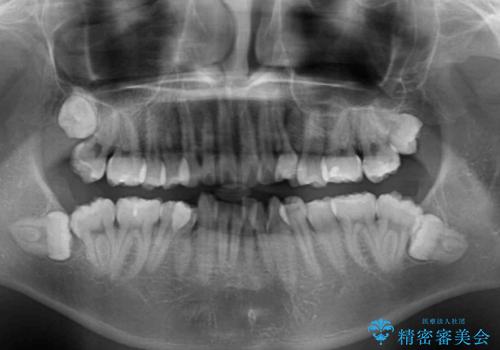

- 前歯の叢生と八重歯を気にして来院された患者様です。

叢生が強く、奥歯の咬合も左右差が大きかったため、上下左右4本を抜歯して、ワイヤー矯正を行うこととしました。